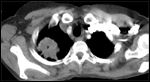

CT scan showing a Pancoast's tumor (labeled as P, non–small-cell lung carcinoma, right lung), from a 47-year-old female smoker. Source: User Jmarchn, Wikimedia Commons